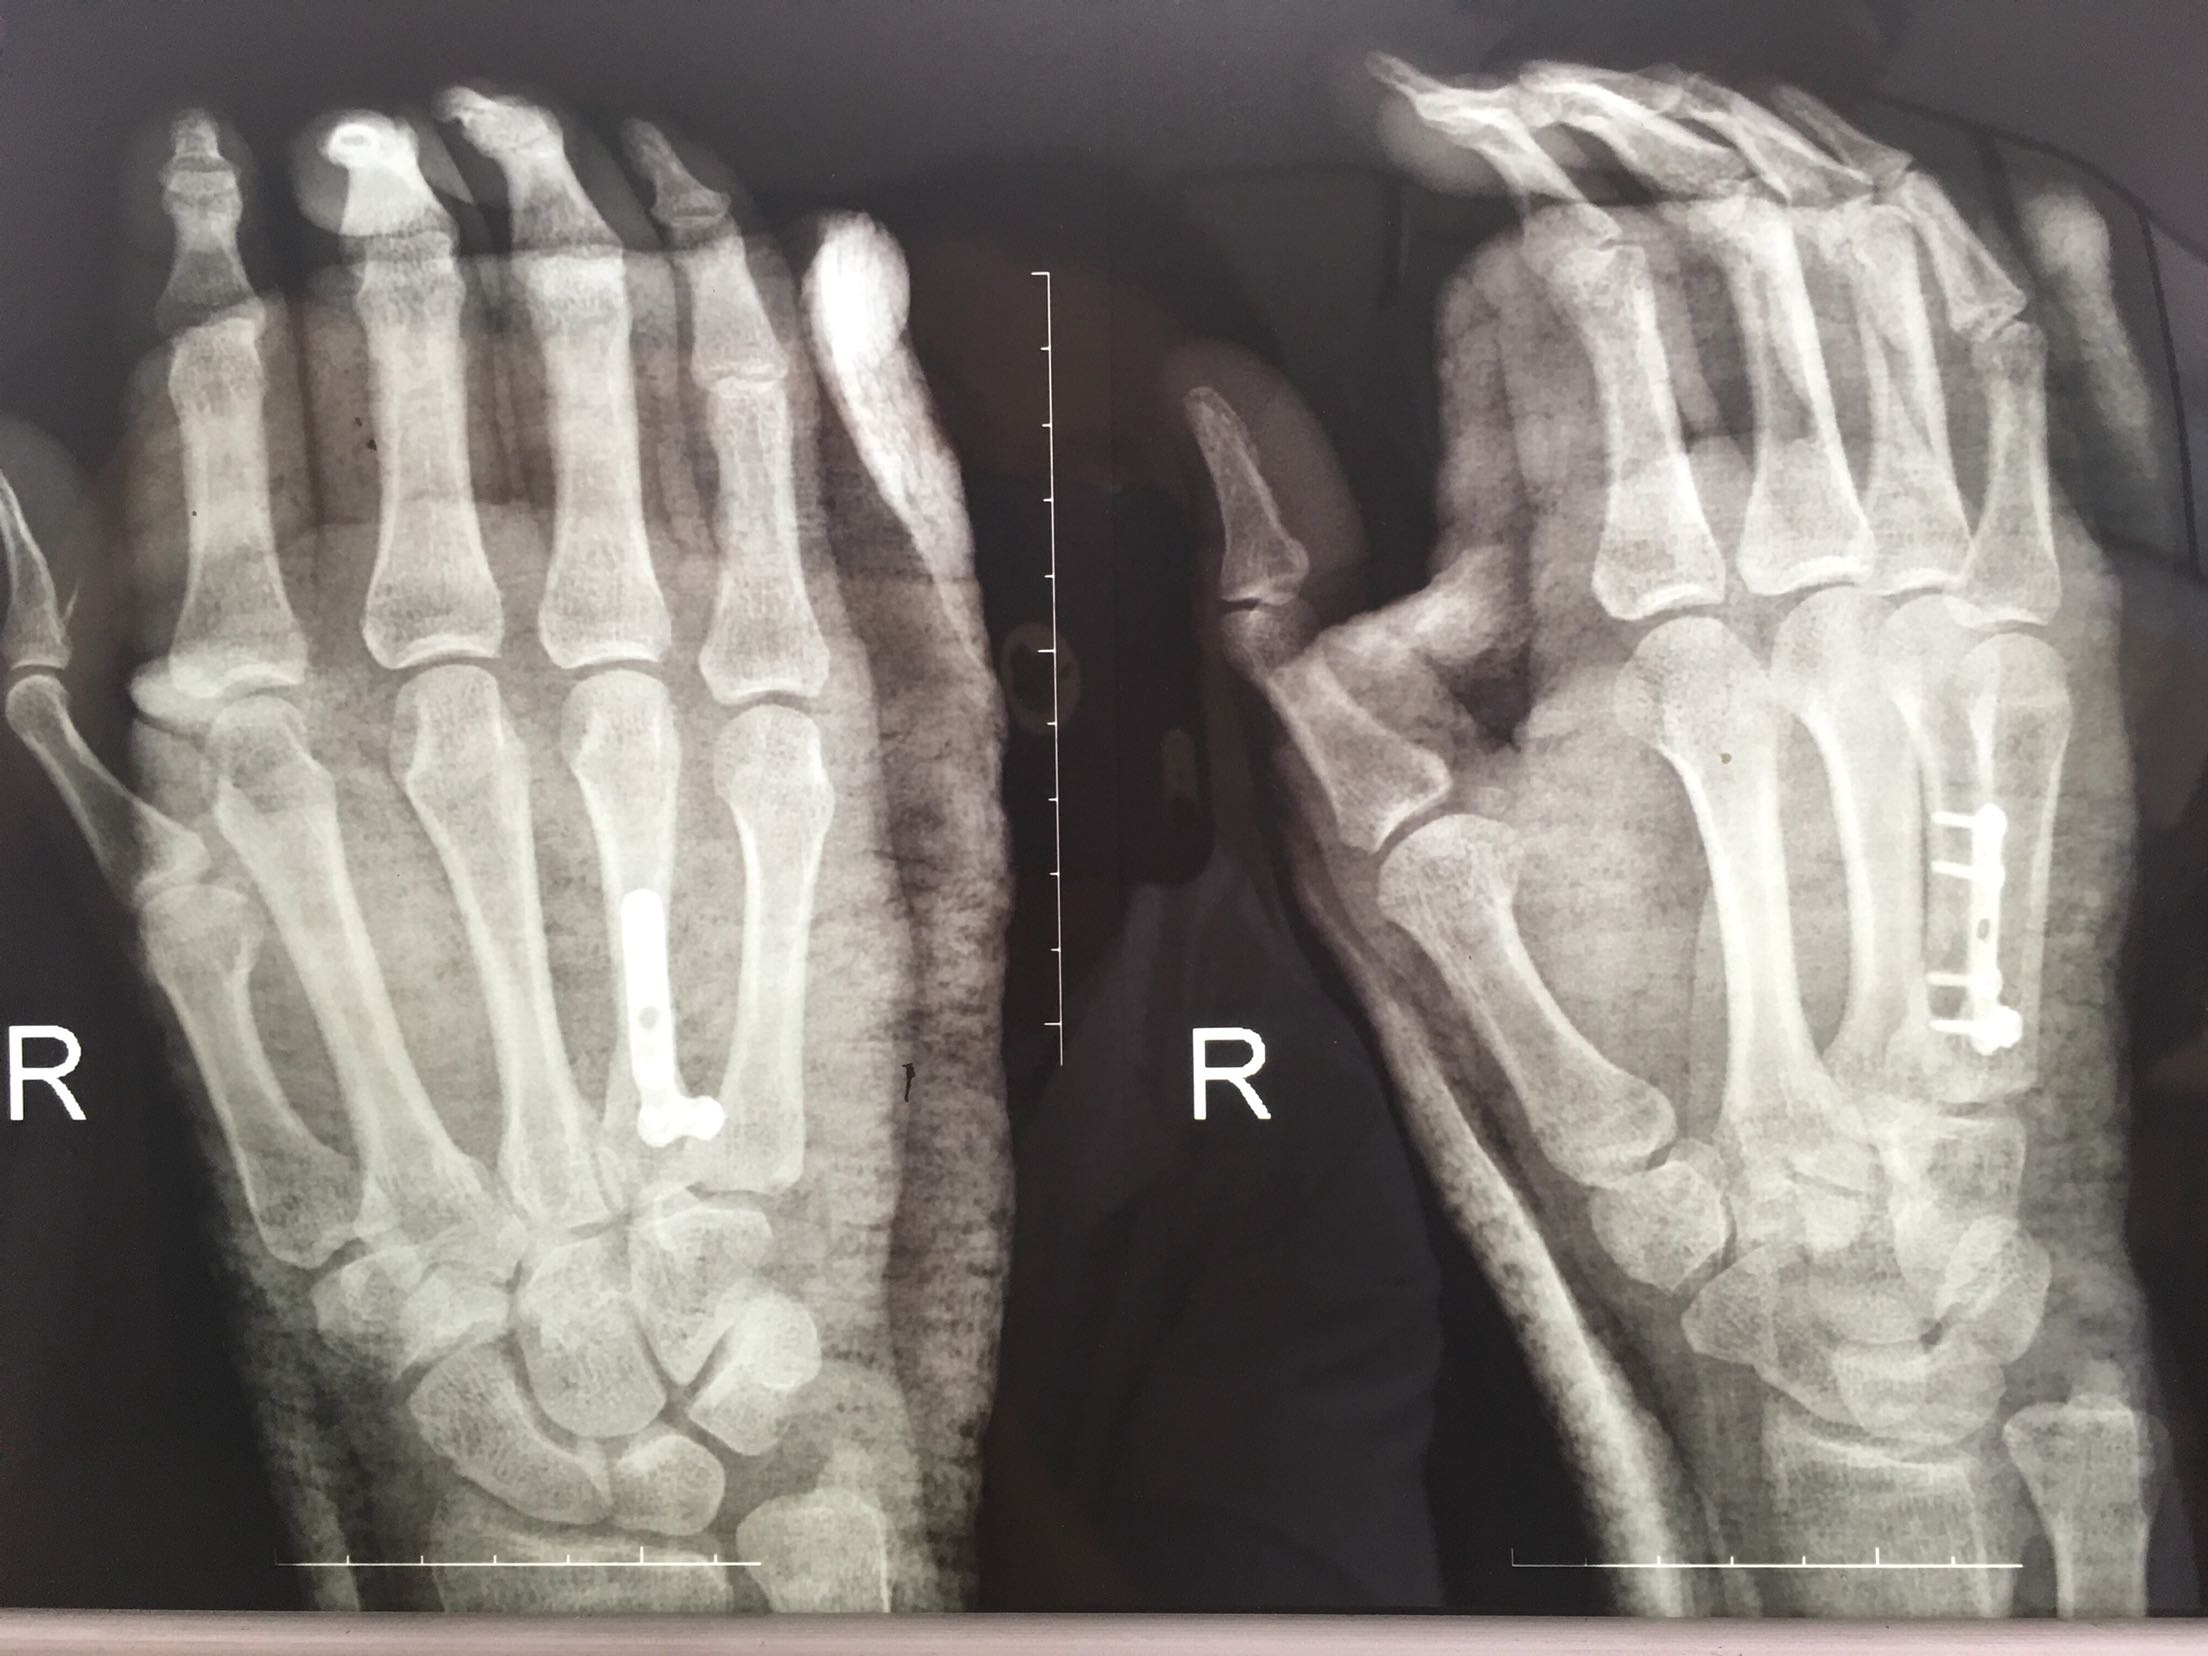

掌骨骨折微钢板固定

完善检查,在臂丛麻醉下行切复内固定术,术后抗炎,消肿止痛处理。

钢板固定的手术风险?望各位老师指正?谢谢